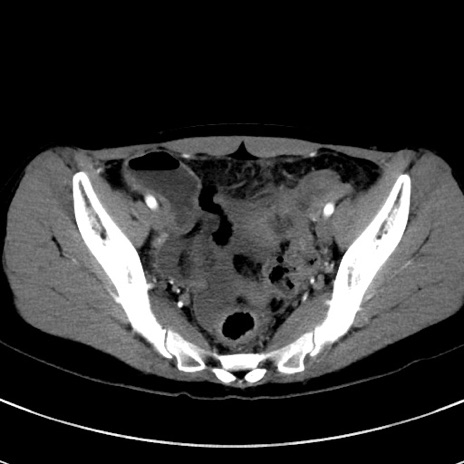

症例17(横断像)

【症例】20歳代女性

【主訴】嘔吐、下腹部痛

【現病歴】昨日夕食後に嘔吐し下腹部痛が出現。本日になっても嘔吐持続し改善しないため来院。

【身体所見】意識清明、BT 37.2℃、BP 108/67mmHg、腹部:平坦、やや硬、下腹部正中から右にかけて圧痛あり、反跳痛軽度あり、tapping pain(+)。

【データ】WBC 13600、CRP 14.94